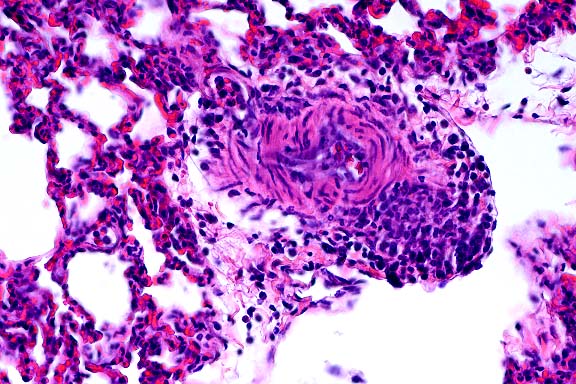

- Case 16-2. Lung. Interlobular septa are markedly expanded

by edema fluid.

- In the tissue section of this experimentally infected animal,

the pulmonary parenchyma is multifocally atelectatic, and the

interlobular septa and subpleural spaces are moderately to severely

expanded by edema and very mild inflammation (lymphocytes, plasma

cells, and neutrophils). Small to medium-sized arterioles throughout

the tissue are lined by endothelium in which the nuclei are prominent

and rounded, are darkly basophilic, bulge into the vascular lumina,

and contain darkly amphophilic viral inclusion bodies. Many of

these arterioles contain sloughed luminal endothelial cells admixed

with moderate numbers of mononuclear and polymorphonuclear cells,

and in some of the arterioles, inflammation extends into the

vessel wall where it is admixed with rare, brightly eosinophilic

hyalinized material (fibrinoid necrosis). Throughout the remaining

parenchyma there is multifocal atelectasis, alveolar capillaries

are expanded by neutrophils, and there is expansion of alveolar

septa by moderate numbers of neutrophils and lymphocytes. Transmission

electron microscopy demonstrated endothelial cell necrosis in

the lungs and alimentary tract and adenovirus particles in the

nuclei with protein crystalline arrays.

- Case 16-2. Lung. The pulmonary arteriole (20x view)

is expanded by lymphocytes and plasma cells. The endothelium

(both views) is lined by piled up, hypertrophic, endothelial

cells which rarely bear smudgy amphophilic intranuclear inclusions

(arrow head).

- AFIP Diagnosis: Lung: Endothelial degeneration and

hypertrophy, diffuse, with multifocal vasculitis, interstitial

pneumonia, diffuse edema, and endothelial intranuclear inclusion

bodies, black-tailed deer (Odocoileus hemionus columbianus),

cervid.